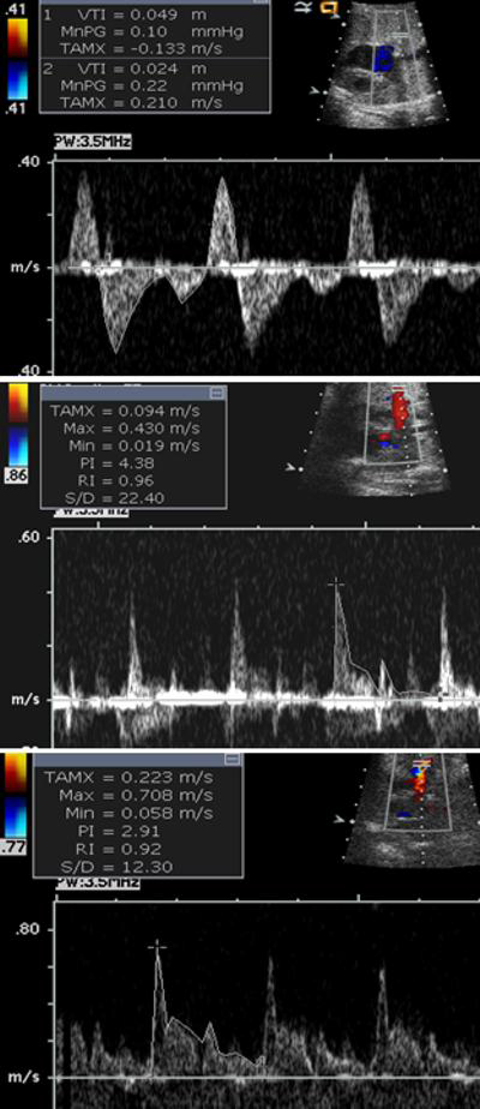

HLHSは出生後,血行動態的にFO開存が不可欠な疾患であるため,胎児心エコーにおいても従来はFOの形態を直接評価していた.一方で,Taketazuらは2004年に,FO自体でなく肺静脈血流パターンの評価の方が生後の状態をよく反映することを報告した33).具体的には胎児HLHS 40例において,肺静脈血流速度信号の面積(=Velocity Time Integral(VTI))を計測し,その逆行性血流と順行性血流の比(VTIR/VTIF)が0.18未満(A),0.18以上(B),拡張早期順行性血流のないto-and-froパターン(C)の3パターンに分類した(Fig. 5).その結果,生後BではAより卵円孔が有意に小さく,Cは全例卵円孔閉鎖しており生直後に緊急処置を要し予後不良であったと述べている.その後,2005年にMichelfelderらが胎児HLHS 41例をまとめた報告では,肺静脈血流パターンはもっと多様であるとしているが,やはり肺静脈血流により生後緊急BAS(Balloon atrio-septostomy)の必要性が予測できたとしている35).2008年にChintalaらも胎児HLHS(FO狭小化のない)27例と正常胎児66例の肺静脈血流パターンを比較して,FO狭小化がなくてもHLHSにおいては肺静脈血流パターンが異なっていることを報告している36).いずれの報告もHLHSにおいては肺静脈血流パターンの確認が重要であると結論している.

母体への酸素投与によるPIの変化については,2002年にBrothらが肺低形成の胎児29例において,母体酸素投与に反応した(PIが20%以上低下した)群15例では生後1例のみ死亡に対し,反応しなかった群では14例中11例が死亡したことより,母体酸素投与によるPIの変化が肺低形成の予測因子となりうることを報告した37).心疾患児に対しては,2010年にSzwartらは43例のHLHS胎児の母体に対し60%酸素10分間吸入の前後で肺動脈のPIの低下10%をカットオフ値として,生後緊急BASを要したrestrictive群と心房中隔が開存していた群に分類できた(感度100%,特異度94%)と報告した34)(Fig. 6).2016年にはEnzensbergerらが22例のHLHS胎児の母体に対し100%酸素10分間吸入前後での肺静脈PIを計測することによって,酸素負荷により胎児FO閉鎖もしくは狭小化の6例中2例でPI低下,つまり血管抵抗の低下により肺還流が増加し,酸素負荷が胎児HLHSの肺血管障害の評価の一助になりうることを示唆した38).